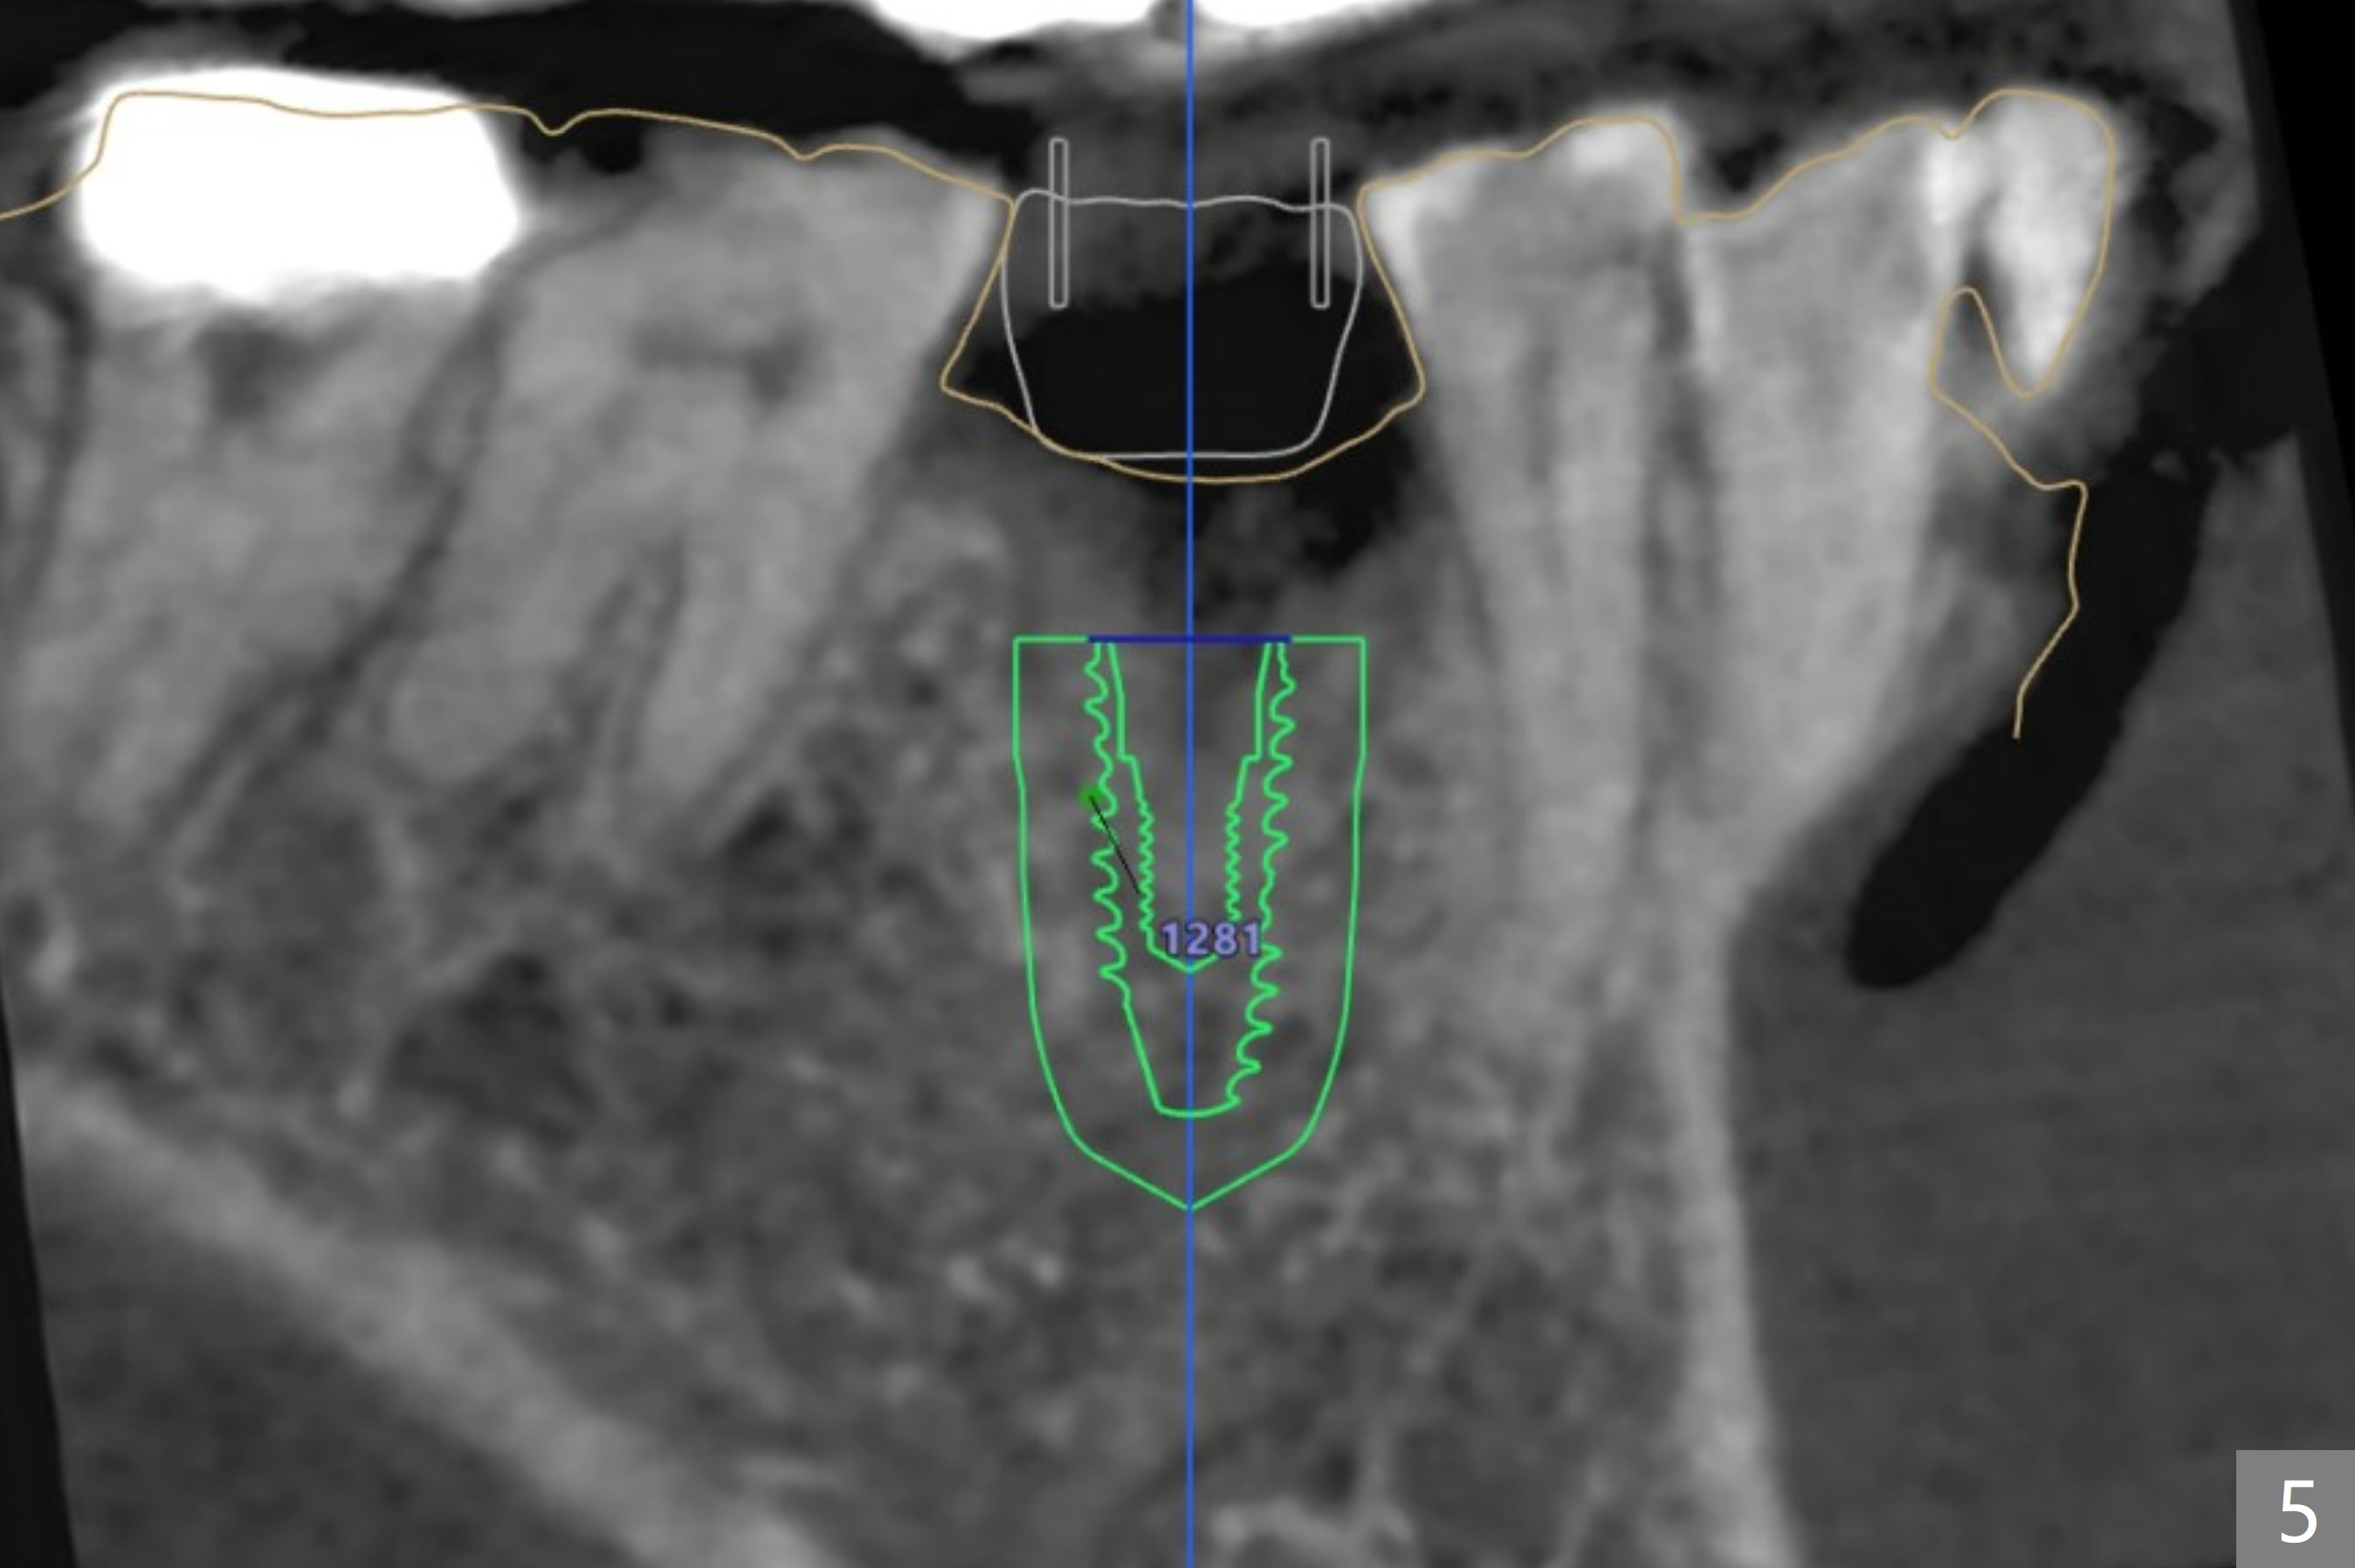

A 77-year-old woman

Return to No Deviation  Xin Wei, DDS, PhD, MS 1st edition 03/04/2021, last revision 05/12/2021